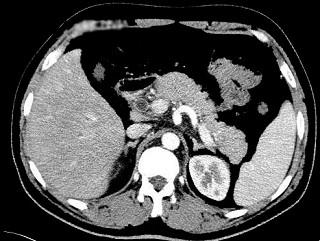

问题 有关急性胰腺炎,哪项是不正确的 ( )

选项 A、有的病例可转为慢性胰腺炎 B、白细胞一般均升高 C、一经确诊应立即手术 D、重症者血清和尿淀粉酶有时不升高 E、水肿性最多见

答案 C